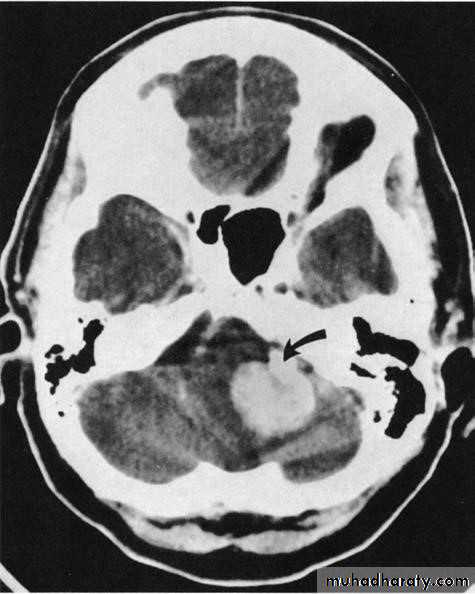

CT scanning demonstrates :

▪ cerebral tumours▪ intracerebral haemorrhage and infarction

▪ subdural and extradural haematoma

▪ free blood in the subarachnoid space (subarachnoid haemorrhage)

▪ lateral shift of midline structures and displacement/enlargement of the ventricular system

Abnormal tissue density

• Abnormal tissue may be of higher or lower density than the normal surrounding brain.• High density is seen with recent haemorrhage, calcified lesions, and areas of contrast enhancement

• Low density is usually due to neoplasms or infarcts, or to oedema, which commonly surrounds neoplasms, infarcts, haemorrhages and areas of inflammation.